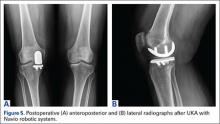

Compared to conventional UKA, robotic assistance has consistently demonstrated improved surgical accuracy, even through minimally invasive incisions (Figures 4, 5).6,20-28 Several studies have found substantial reduction in variability and error of component positioning with use of semiautonomous robotic tools.6,21,25 In fact, precision appears to be comparable regardless of whether an image-free system or one requiring a preoperative CT scan is used (Table). Further, in addition to improving component and limb alignment, Plate and colleagues22 demonstrated that RAS-based UKA systems can help the surgeon precisely reproduce plans for soft-tissue balancing. The authors reported ligament balancing to be accurate up to .53 mm compared to the preoperative plan, with approximately 83% of cases balanced within 1 mm of the plan through a full range of flexion.22